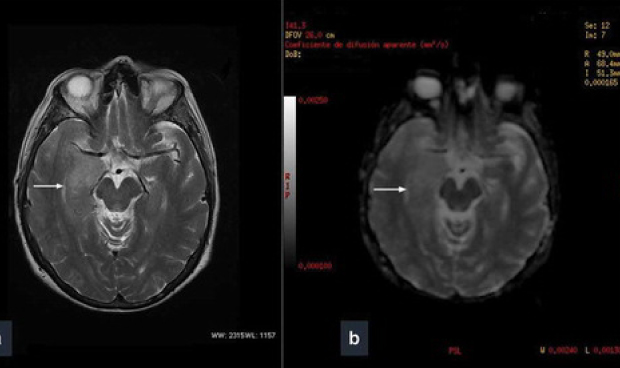

Lóbulo temporal derecho, posible culpable

A pesar de que en el estudio se indica que no se ha identificado qué parte del cerebro ha sido la responsable de las experiencias místicas de la paciente, se tiene la hipótesis de que haya podido ser el lóbulo temporal derecho.